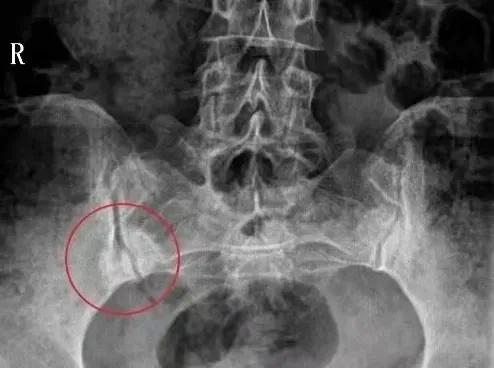

影像學表現